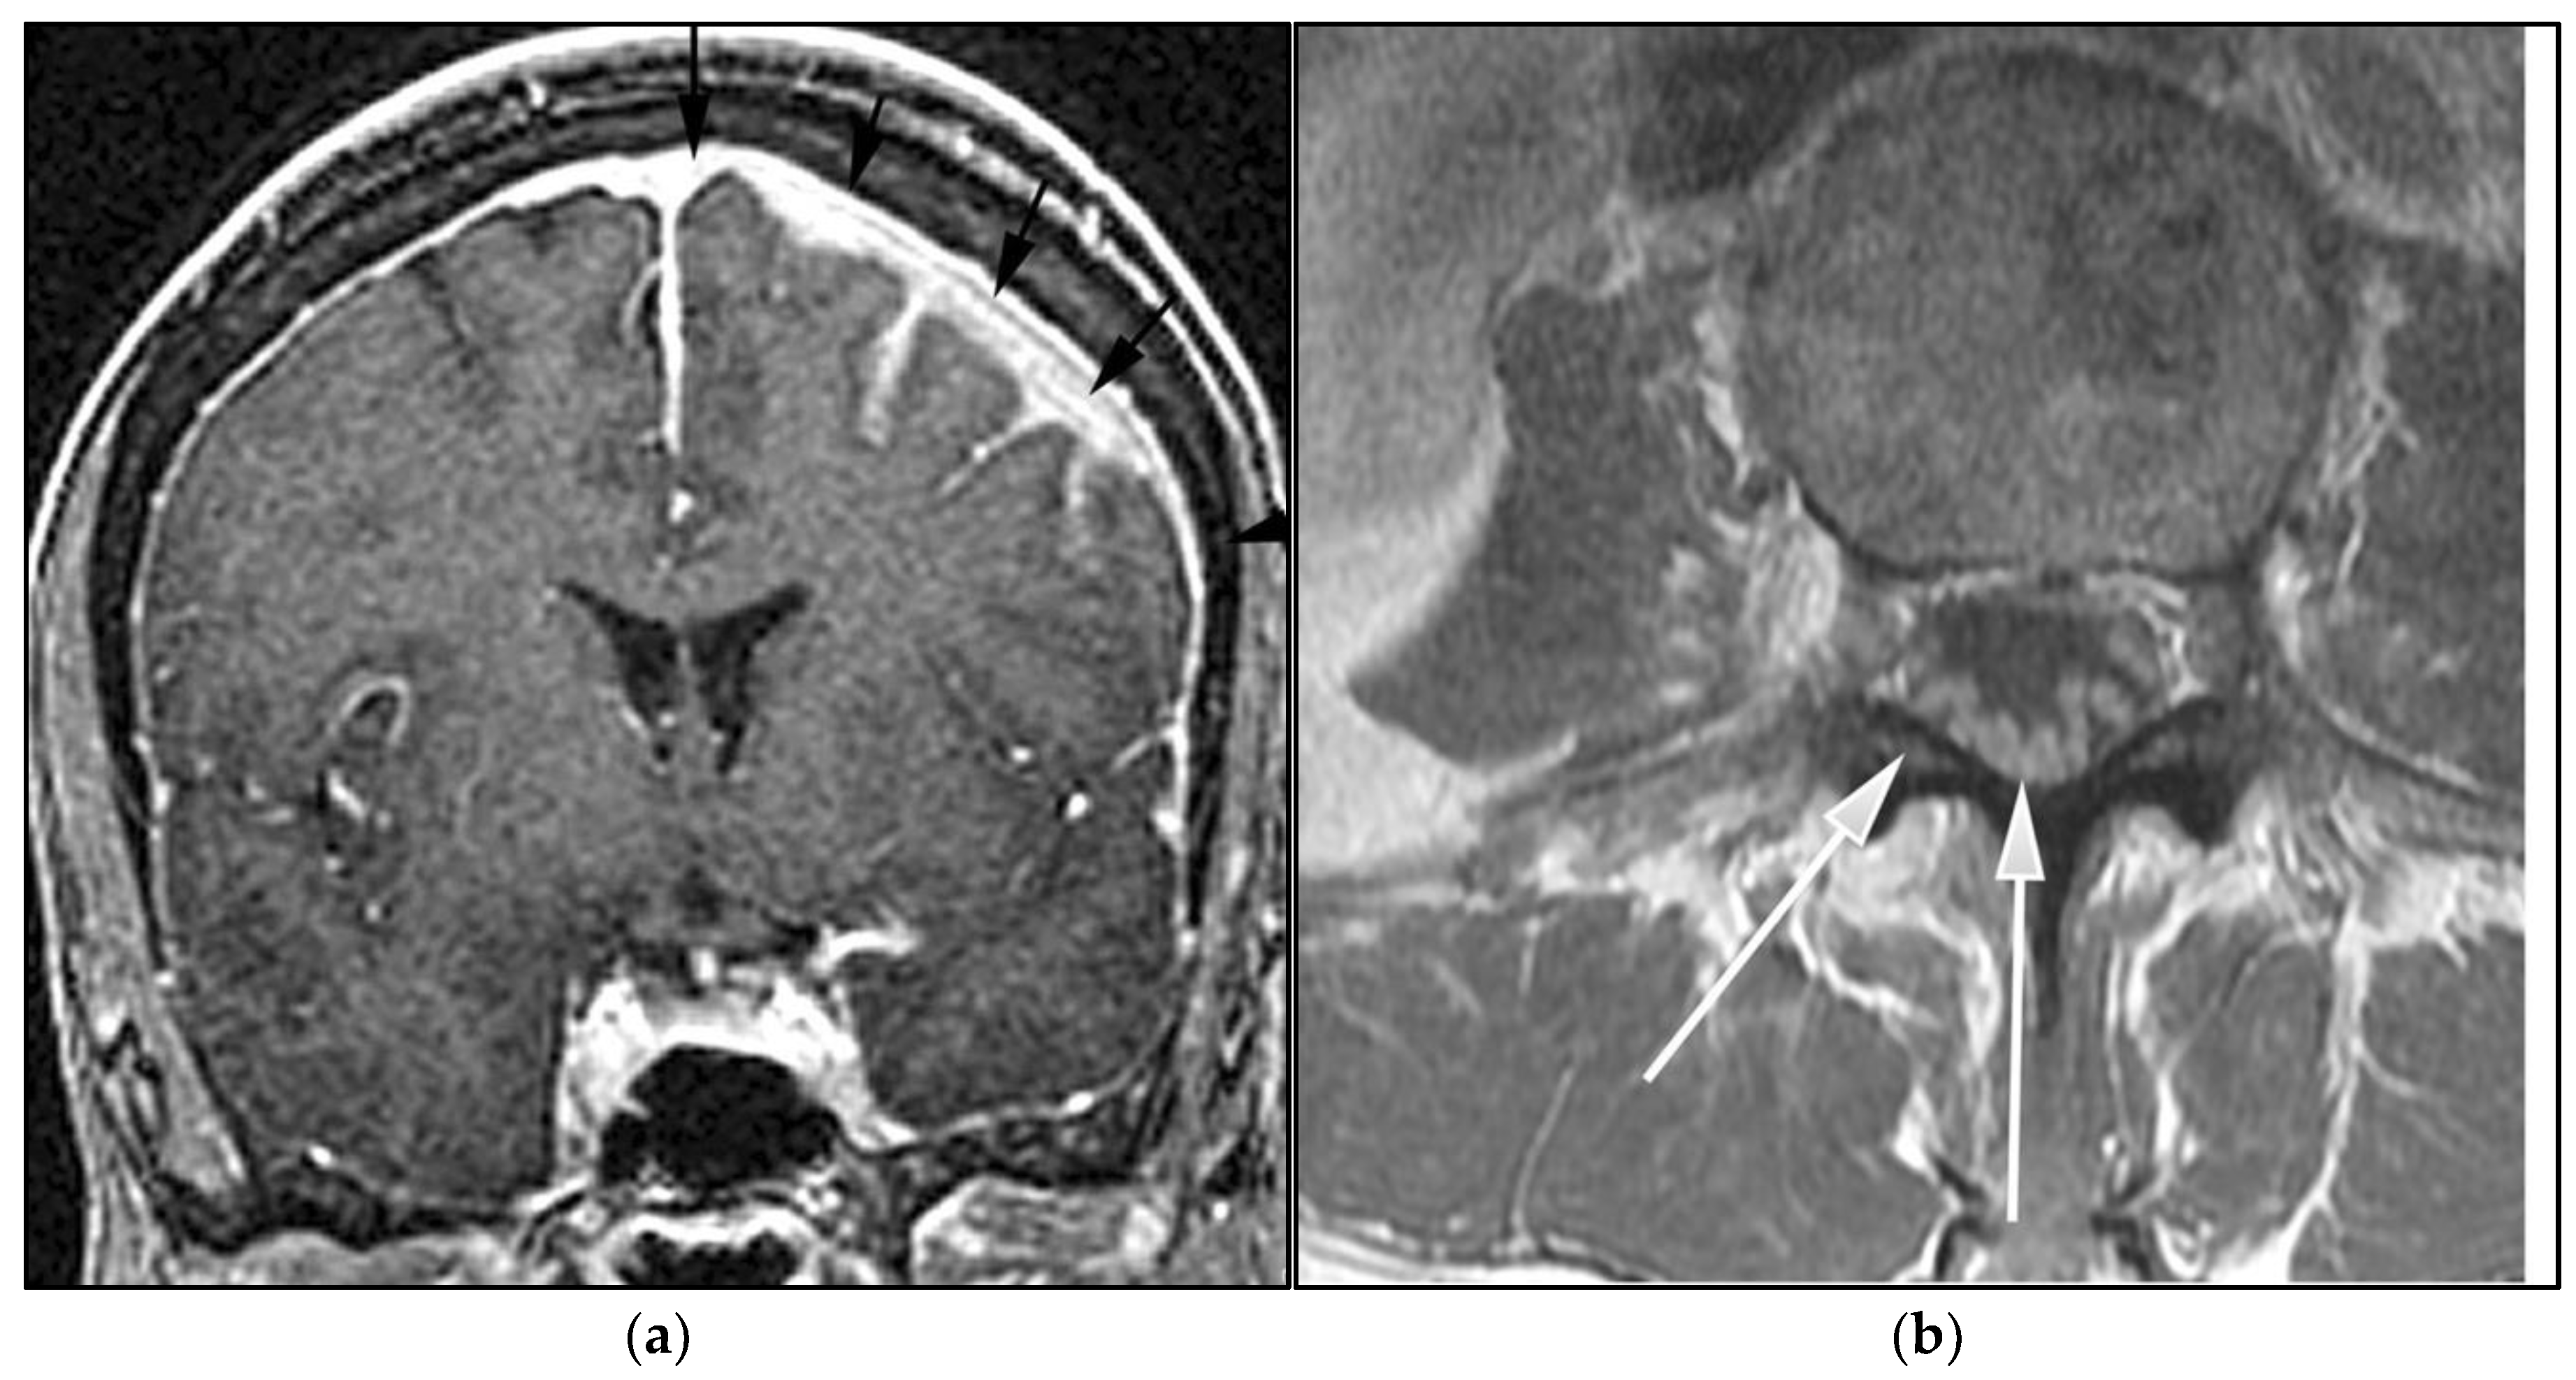

Figure 2.

A 64-year-old-woman presenting with rapid onset of memory deterioration and altered sensorium. (a) Coronal MRI T1 post-contrast images show subtle enhancement along bilateral deep nuclei. At this time, no diagnosis was determined. After 3 weeks, patient presented to emergency department with worsening symptoms. A follow-up MRI was performed. (b) Coronal MRI post-contrast fat-saturated images revealed progressive increase in extent of diffuse infiltrative enhancing masses (white arrows).

Figure 3.

Same MRI series. (a) Axial post-contrast MRI image shows lesions extending caudally to involve the bilateral superior cerebral peduncles and anterior aspect of the mid-brain. (b) Axial MRI T1 post-contrast fat-saturated images show involvement of the posterior limb of the internal capsule and the thalami bilaterally (white arrows). (c) Extension along the lateral aspect of the pons, dentate nucleus, and the middle cerebellar peduncles (white arrows). (d) Axial FDG fused PET/CT image shows increased activity in the aforementioned lesions. Additional hypermetabolic lesions are seen along the course of the corticospinal tract (white arrows). Imaging findings and pattern of involvement are consistent with lymphomatosis cerebri. (e) H&E section shows a tumor composed of large and pleomorphic cells with intermingled small lymphocytes. Primacy CNS lymphoma typically demonstrates an angio-centric predilection. (Original magnification 400×, H&E stain). Other differential diagnoses include a vasculitic process, toxic or metabolic encephalopathy, paraneoplastic syndrome, or acute disseminated encephalomyelitis. Biopsy showed a large non-cohesive B-cell lymphocyte population consistent with LC.